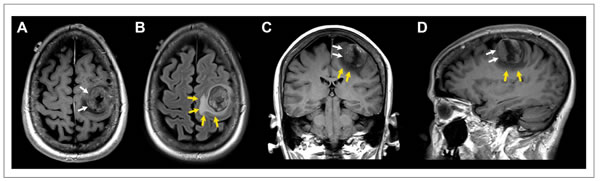

A total of 20 breast cancer cases met the study criteria. These included 11 breast cancer cases with brain metastasis and 9 age, stage and follow-up matched breast cancer cases without brain metastasis [12]. Figure 1 shows the typical radiographic features of a patient who underwent resection of a solitary breast cancer brain metastasis.

Figure 1: Patient with solitary breast cancer brain metastasis involving the posterior aspect of the left middle frontal gyrus. Post-contrast T1-weighted axial (A), coronal (C), and sagittal (D) images and fluid-attenuated inversion recovery (FLAIR) axial image (B) showing a 2.5 × 3.3 × 3.1 cm mass (white arrows) with extensive peritumoral vasogenic edema (yellow arrows). Of note, this patient had the highest expression of miR-20b in the resected tumor specimen.